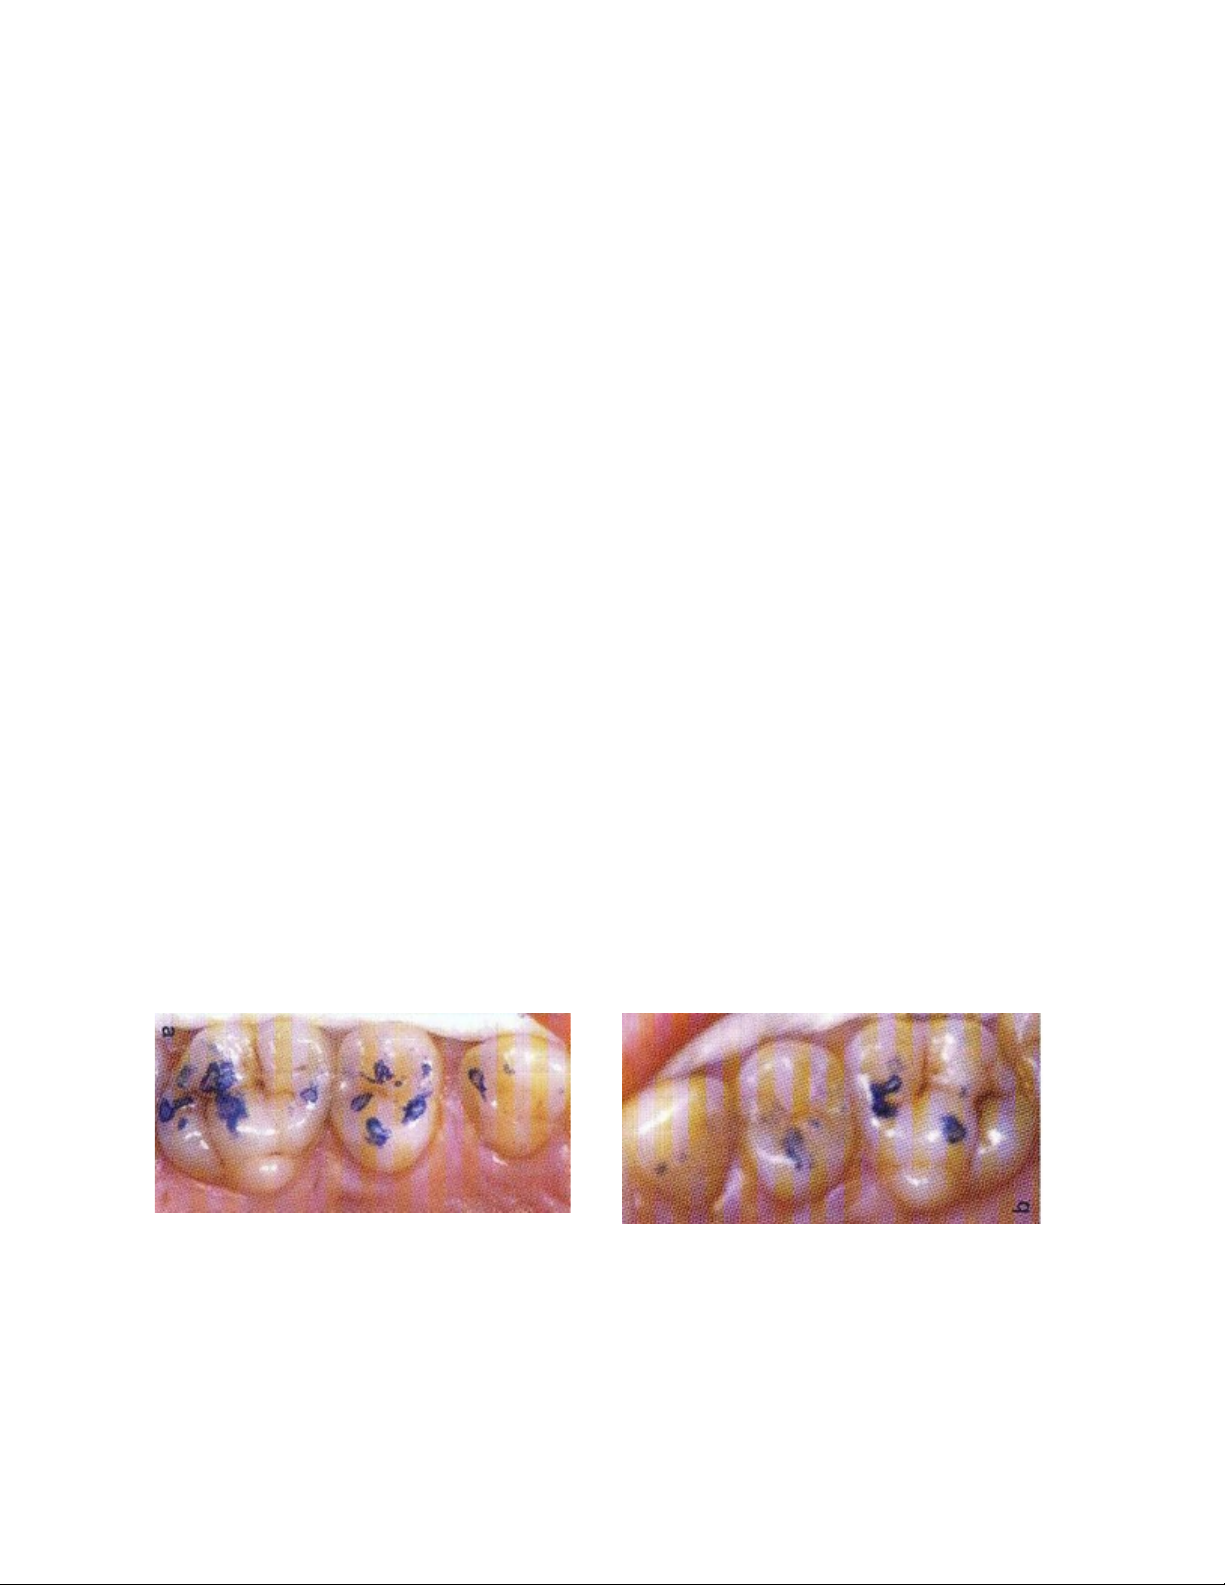

3.Phương pháp loại bỏ các điểm chạm quá mức

Các điểm chạm quá mức, được xác định bởi giấy cắn, đặc trưng bởi các bề

mặt cùng cường độ nhưng quá rộng hoặc những vùng có cường độ quá mạnh (hình

vẽ)

Hình : Điểm chạm cắn quá rộng trên

răng 16

Hình : Điểm chạm cắn có cường độ

quá mạnh trên răng 26

Hình : Điểm chạm cắn ở khớp

cắn chạm múi tối đa

Nhìn mặt nhai xuất hiện các điểm

chạm quá rộng trên răng 16 và

răng đối đỉnh 46. Mài mặt nào?